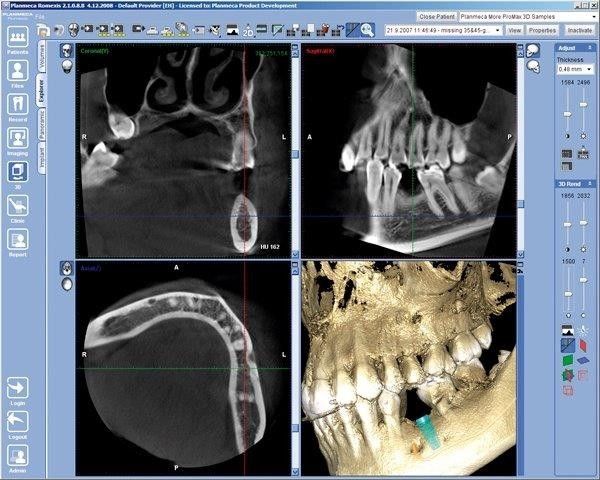

Auf den folgenden Fotos sehen Sie 3D-Röntgenbilder:

• Die dabei entstandene Aufnahme – Ihr Kiefer wird dabei räumlich dargestellt – enthält alle Grunddaten, im Anschluss kann diese mit spezieller Software unterschiedlichen Aufbereitungen zugeführt werden.

• Dank dieser dreidimensionalen Visualisierung eröffnet sich Ihrem Zahnarzt eine bis dato unbekannte Dimension der Diagnostik.